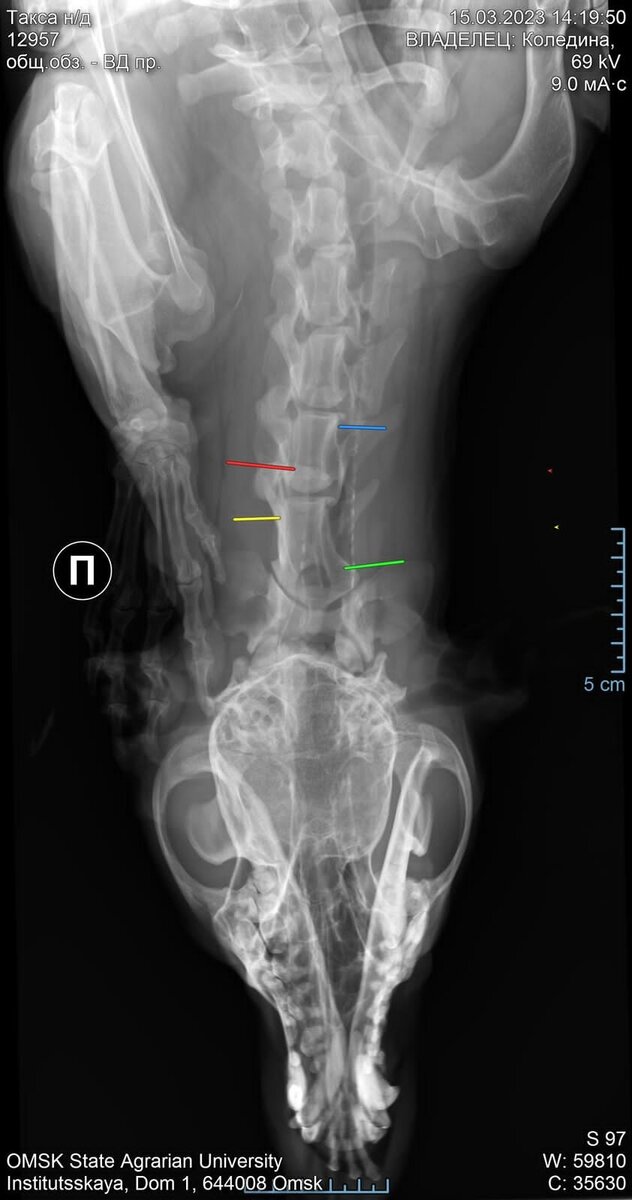

Марсель поступил к нам с множественными гематомами и рваными ранами по всем телу.

Проведя обследование в двух ветеринарных клиниках и сделав рентгенографию, специалисты выявили многочисленные телесные повреждения, а также перелом позвоночника шейного отдела со смещением. Собаку били по голове и даже в область паха...

Обратившись к хирургу-ортопеду ветеринарной клиники "Биота" нам назначили операцию на 19 марта, но рано утром тоже дня в стационаре ветеринарной клиники у собаки произошла остановка дыхания, а затем остановка сердца.